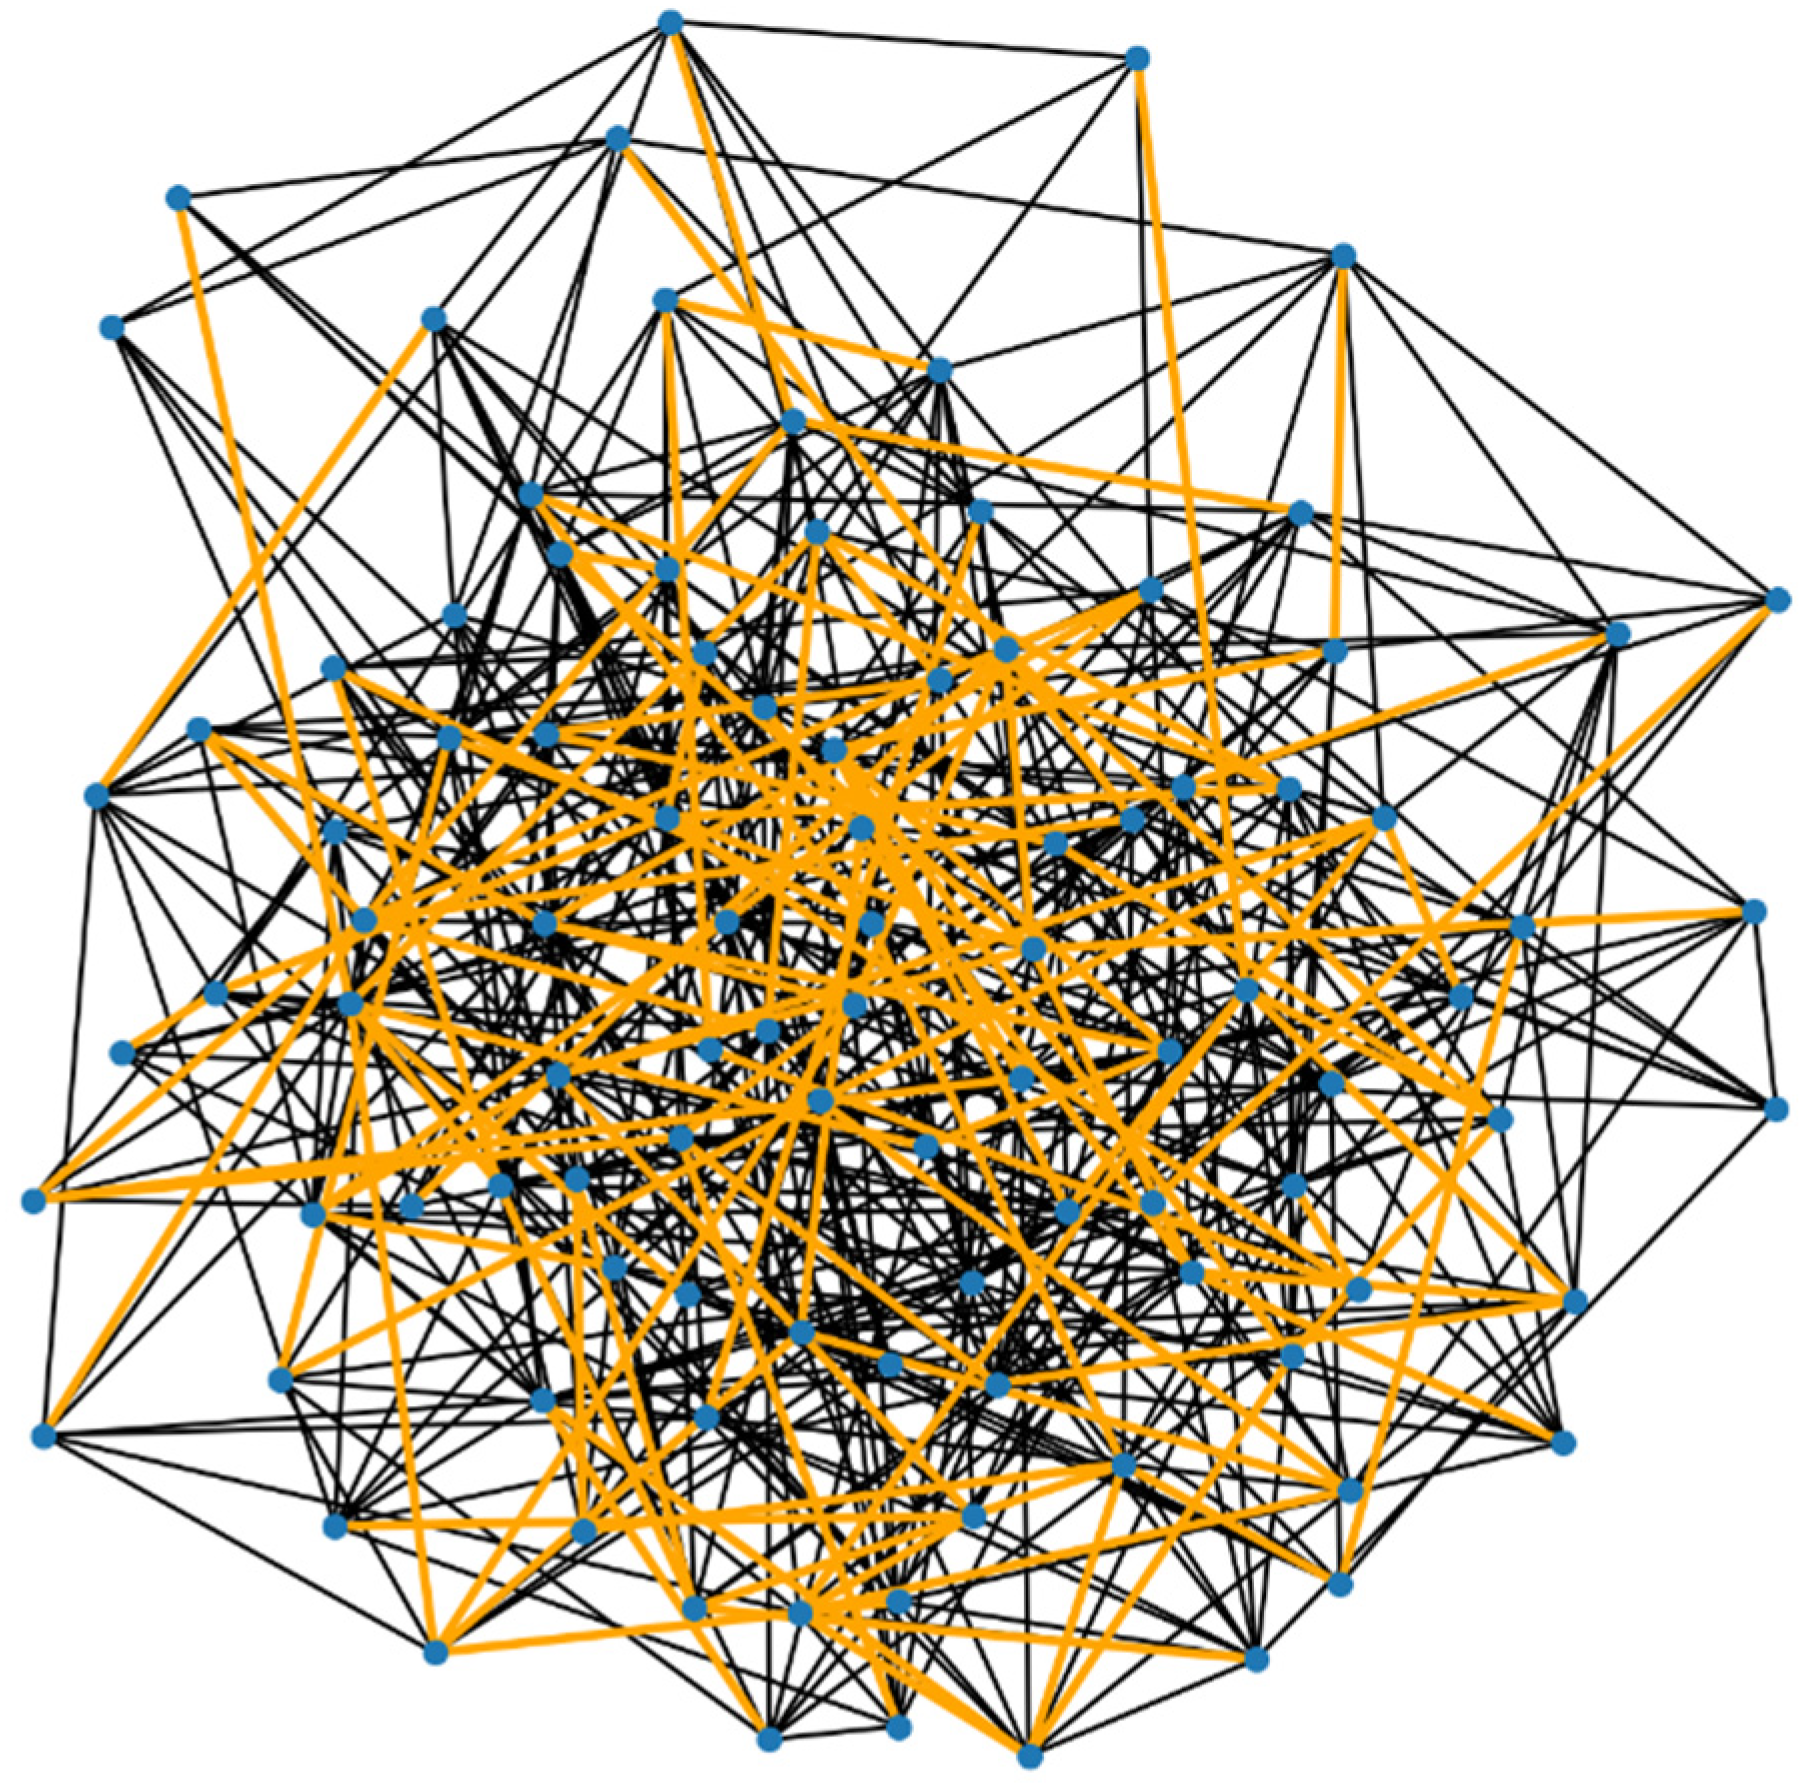

Figure 2. Here is the visualization of the demyelinated neural network, with the demyelinated paths highlighted in orange. In this graph: The normal connections (edges) are shown in the standard color. The connections that have been affected by demyelination (i.e., those with increased resistance) are highlighted in orange.

In the 50% demyelinated network (Figure 3), a significant number of connections are highlighted, indicating a substantial increase in demyelination compared to the previous example. This increased rate of demyelination is reflected in the network’s properties:

Average Shortest Path Length: 2.2852.285

This length is probably longer than in the previously simulated network with a 20% demyelination rate, indicating a further decrease in network efficiency due to the more extensive demyelination. This visualization and metric demonstrate how increasing the extent of demyelination can progressively impact the network’s ability to efficiently transmit signals.